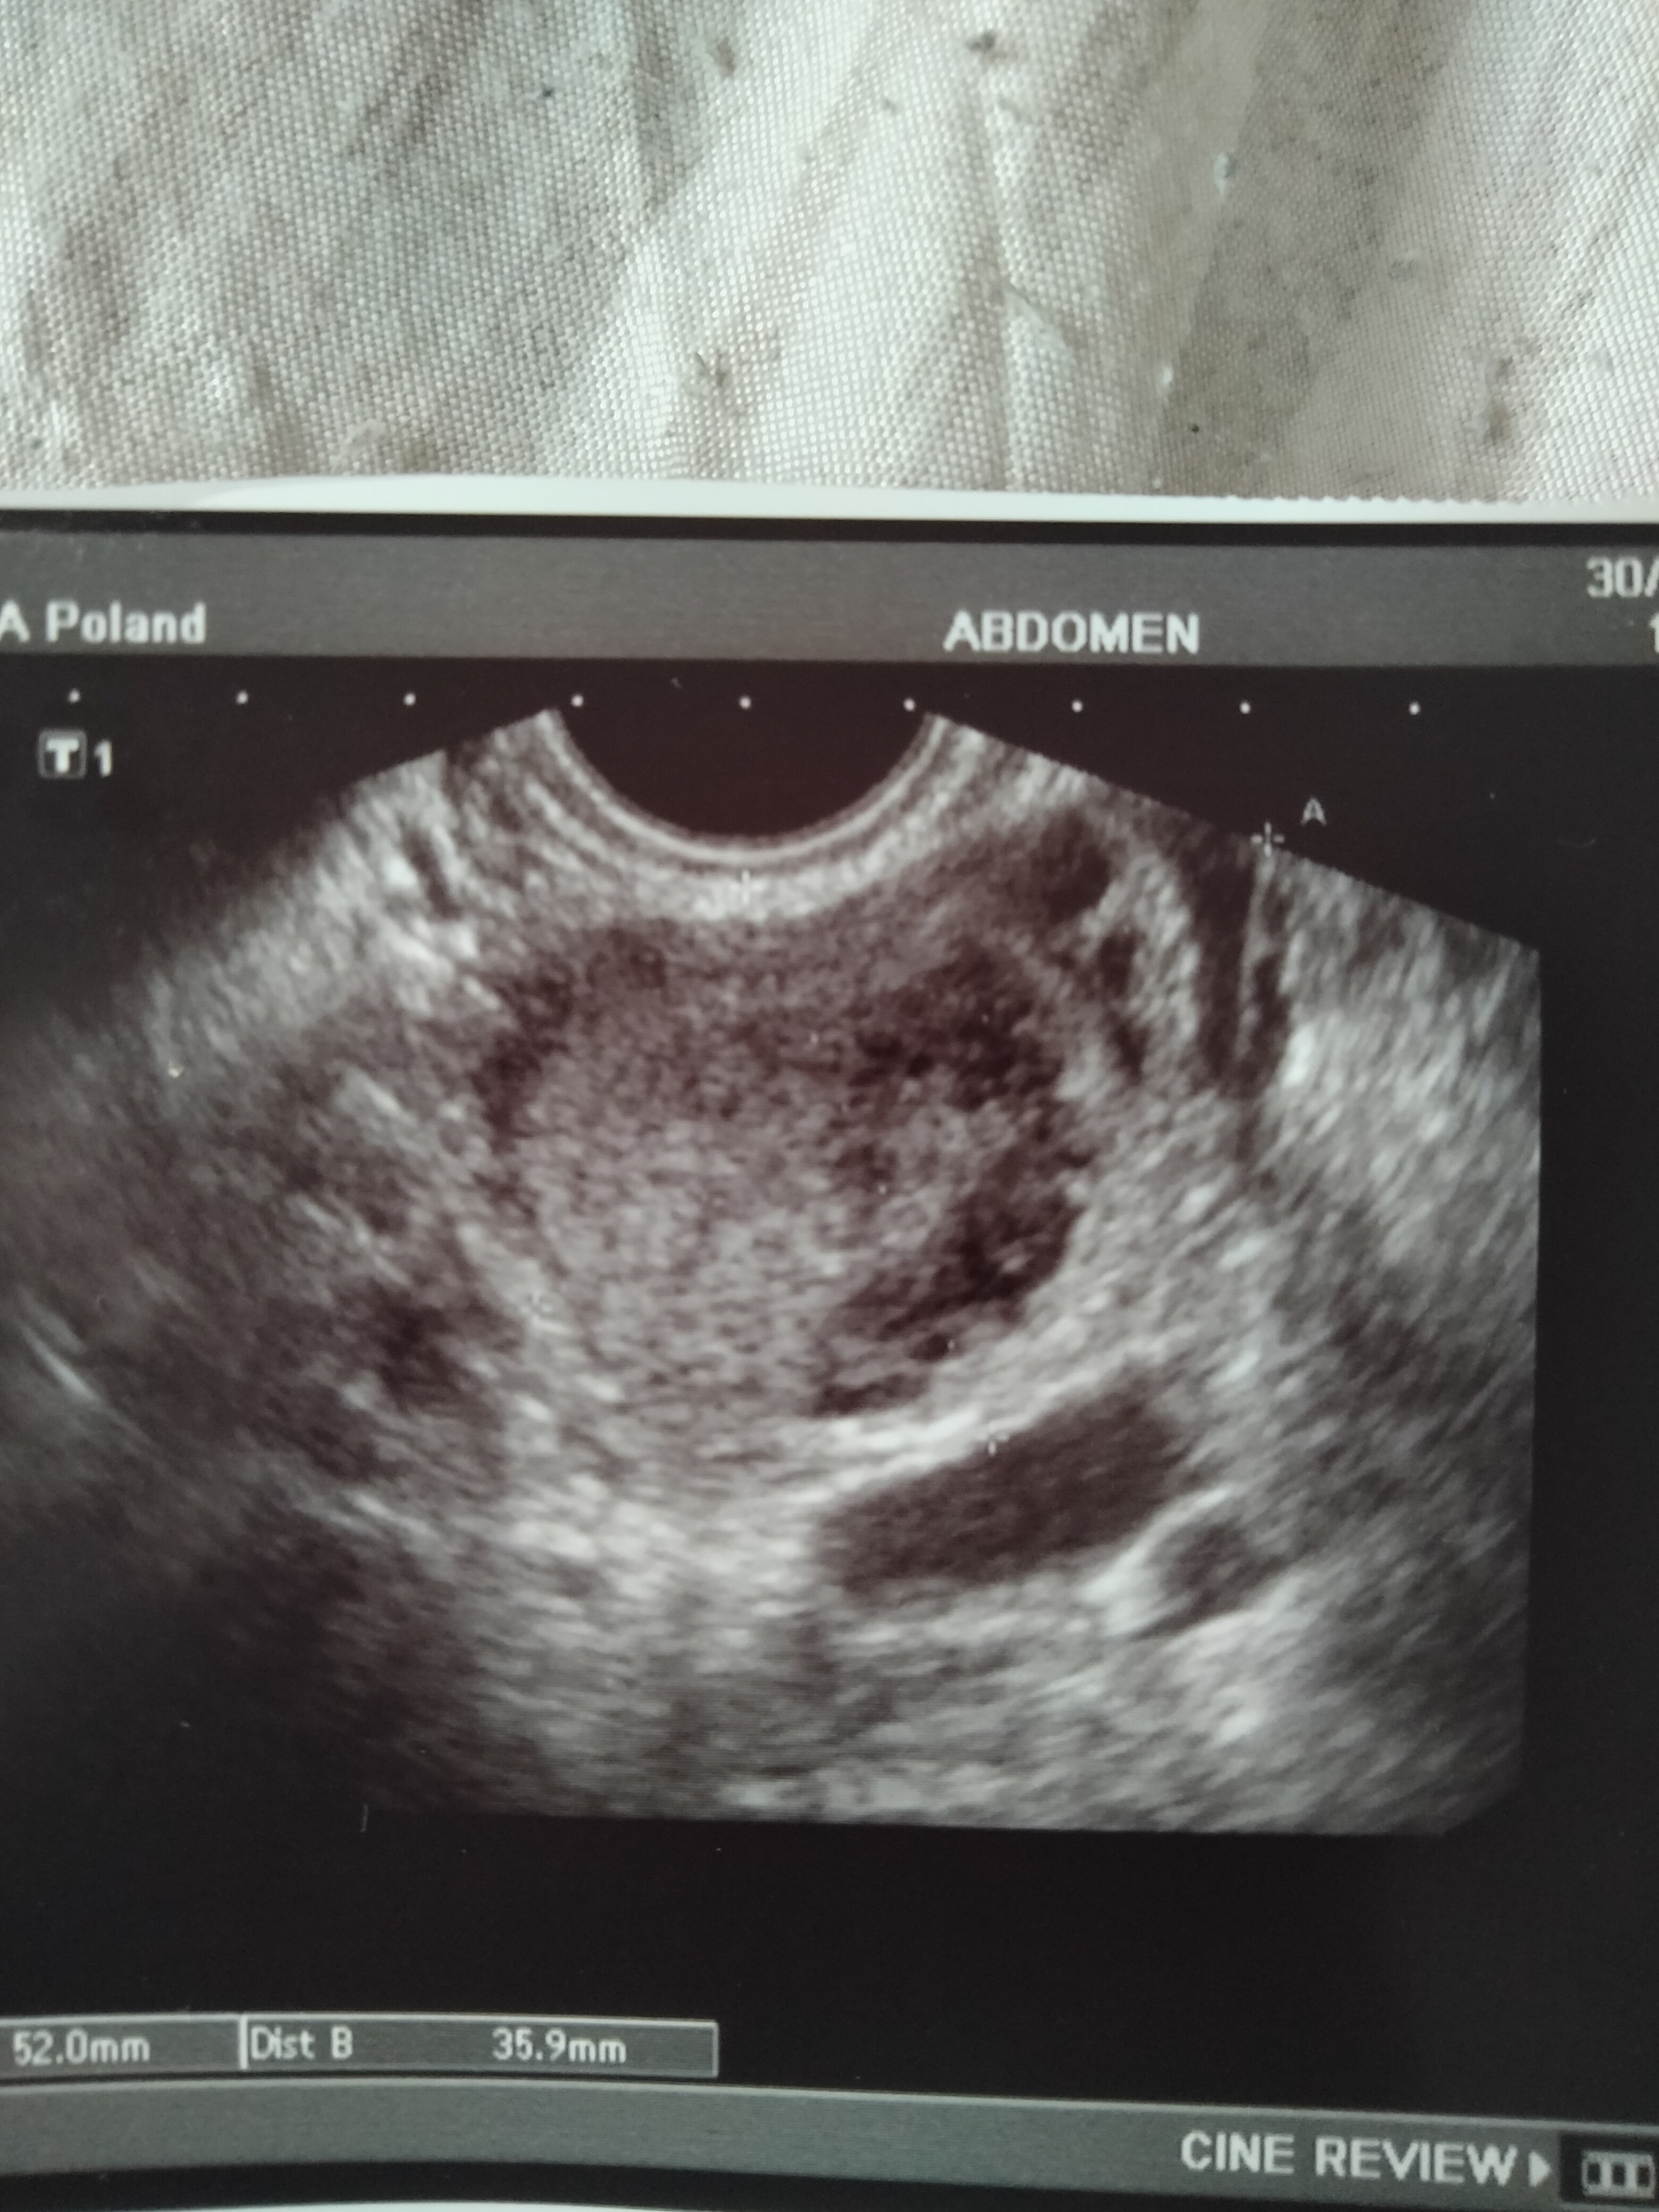

Hej słuchajcie jestem załamana okres spóźnia mi się 4 dzień robiłam test w dniu spodziewanej miesiączki wyszedł mega bladzioch ostatnia miesiączkę miałam 25 lutego moje cykle trwają 31 dni a teraz miesiączkę powinnam dostać 27 marca a po niej śladu nie widać bolą mnie sutki i jajniki byłam dziś u ginekologa stwierdził że to za wcześnie i na USG nic nie widać ponadto dowiedziałam się że mam torbiel na jajniku wstawię zdjęcie USG może ktoś coś się dojrzy